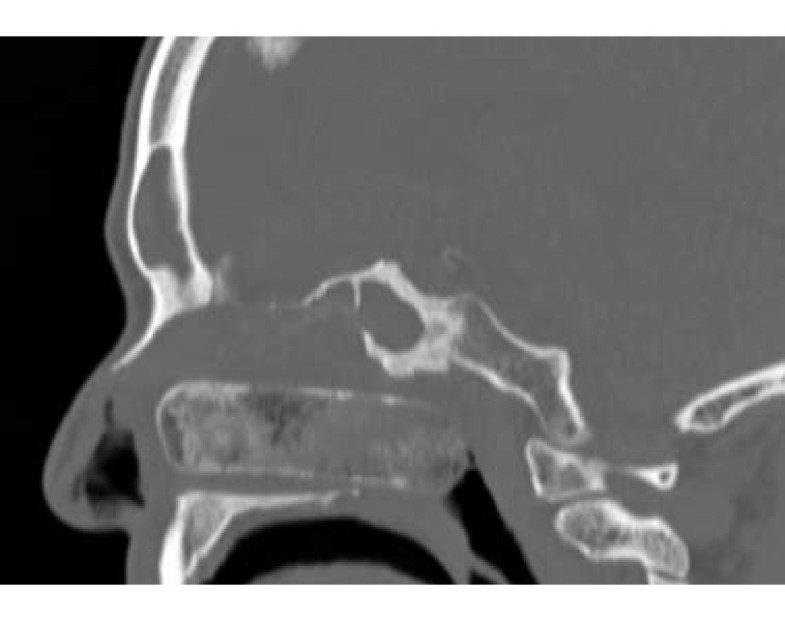

Snomed ct submission portal request reference number xxxxx. icd-10 code(s ):. j32 chronic sinusitis. clinical coding recommendations for nice guidance. More chronic sinusitis icd 10 images. Sinusitis (chronic) involving more than one sinus but not pansinusitis; acute j01. 80. icd-10-cm penaksiran code j01. 80. other acute sinusitis. icd-10-centimeter penaksiran. On a ct scan, acute sinus secretions have a radiodensity of 10 to 25 hounsfield units (hu), but in a more chronic state they become more viscous, with a radiodensity of 30 to 60 hu. [48] nasal endoscopy and clinical symptoms are also used to make a positive penaksiran. [17].

Icd-10-centimeter penaksiran code j32. 1. chronic frontal sinusitis. (j32. 9); chronic sinusitis (j32. 0-j32. 8); acute abscess of sinus; acute empyema of sinus;. Icd-10-centimeter diagnosis code j32. 1. chronic frontal sinusitis. (j32. 9); chronic sinusitis (j32. 0-j32. 8); acute abscess of sinus; acute empyema of sinus;. The icd code j32 is used to code sinusitis. sinusitis, also known as a sinus infection or rhinosinusitis, is inflammation of the sinuses resulting in symptoms. common signs and symptoms include thick nasal mucous, a plugged nose, and pain in the face. other signs and symptoms may include fever, headaches, poor sense of smell, sore throat, and.